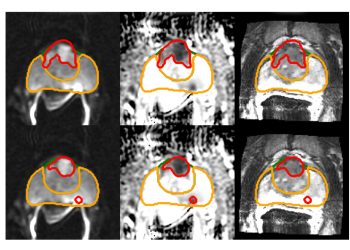

Şekil 1. BrightHeart AI, fetal anatomi taramaları sırasında fetal kalp görüntülerini analiz eder ve potansiyel morfolojik anormalliklerle ilgili geri bildirim sağlar.

BrightHeart, teknisyenlere iş akışlarını geliştirirken yardımcı olurken, ultrason görüntülerindeki önemli morfolojik anormallikleri de takip ediyor. Tespit edilen kalp anormallikleri, müdahale için doktorlara iletiliyor. BrightHeart, AWS üzerinden bulutta NVIDIA L4 Tensor Core GPU’ları kullanarak modellerini eğitim ve tahmin için geliştiriyor.